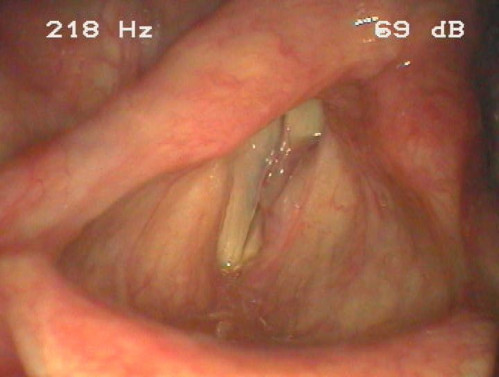

ICD: Q31.3

Eine 63-jährige Patientin klagt über Missempfindungen (Fremdkörpergefühl) auf Höhe des Kehlkopfes. Bei längerem Sprechen empfindet sie Stimmanstrengungen. Atmung und Schlucken sind nicht beeinträchtigt. Sie hat auch keinerlei sonstige Beschwerden oder Erkrankungen.